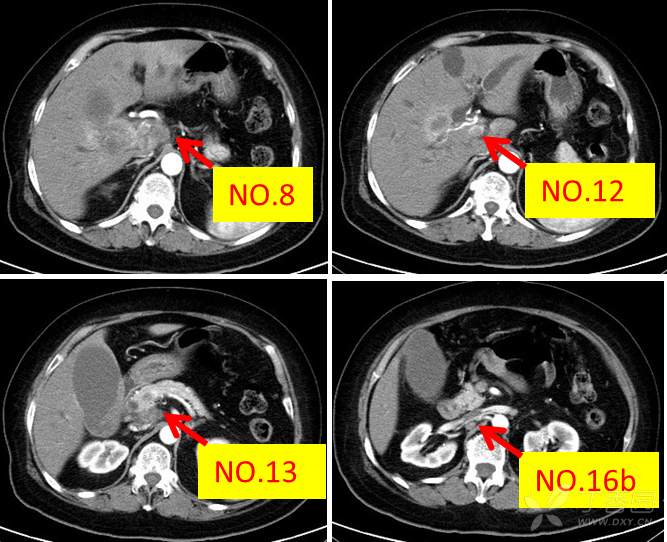

术前淋巴结评估如下:

病情介绍完了,如果是您,怎么安排?我个人觉得伴有多处淋巴结转移的胆囊癌,即使硬着头皮右半肝切除+淋巴清扫,绝大多数效果不好,何况该患者梗黄伴有肝内胆管扩张。